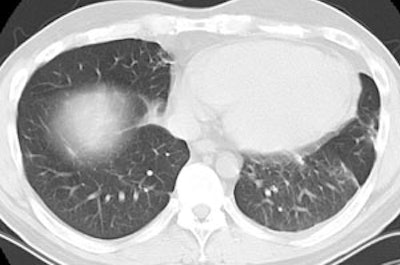

The patient below presented with complaints of cough, malaise, and a low-grade fever. The chest radiograph revealed some patchy left lower lobe airspace disease and vague nodular shadows- particularly in the lower lung zones. A chest CT was performed and demonstrated multiple nodular airspace abnormalities with variable margins. The lesions did not improve despite antibiotic therapy and all cultures were negative. Click images to enlarge.